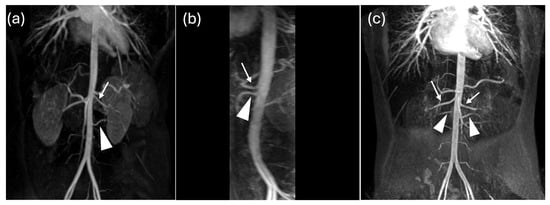

Multiple Renal Arteries as a Potential Contributor to Hypertension in Children and Young Adults

Background: Arterial hypertension in childhood is an increasing health concern, often associated with structural and functional cardiovascular or renal alterations. This study aimed to investigate the prevalence and type of non-stenotic renal artery anatomical variants in children with systemic hypertension and to assess their possible association with cardiac involvement. Methods: A total of 107 children and adolescents with hypertension (mean age 15.4 ± 2.7 years) were evaluated. Hypertension was defined as blood pressure persistently above the 95th percentile for over one year, confirmed by 24 h ambulatory blood pressure monitoring. Patients with known secondary causes were excluded. All underwent renal vascular imaging by CT or MRI and echocardiographic assessment of left ventricular morphology and function. Results: Renal artery anatomical variants were found in 69 of 107 patients (65%), mainly unilateral or bilateral accessory polar arteries. Other anomalies found (left renal vein narrowing or duplication, severe left renal artery stenosis) were excluded from the statistical analysis. Normal renal vasculature was observed in only 32%. Left ventricular hypertrophy was detected in 41%, highlighting a significant prevalence of target-organ involvement. No statistically significant differences were found in terms of hypertension or hypertrophy between patients with renal artery anatomical variants and those without. However, patients with renal anomalies more frequently required dual antihypertensive therapy (p = 0.025). Conclusions: Renal artery anatomical variants, even in the absence of overt stenosis, may contribute to the pathogenesis of pediatric hypertension and complicate its management. Systematic evaluation of renal vasculature should be considered in the diagnostic workup to improve risk stratification and guide management strategies.

Figure 1